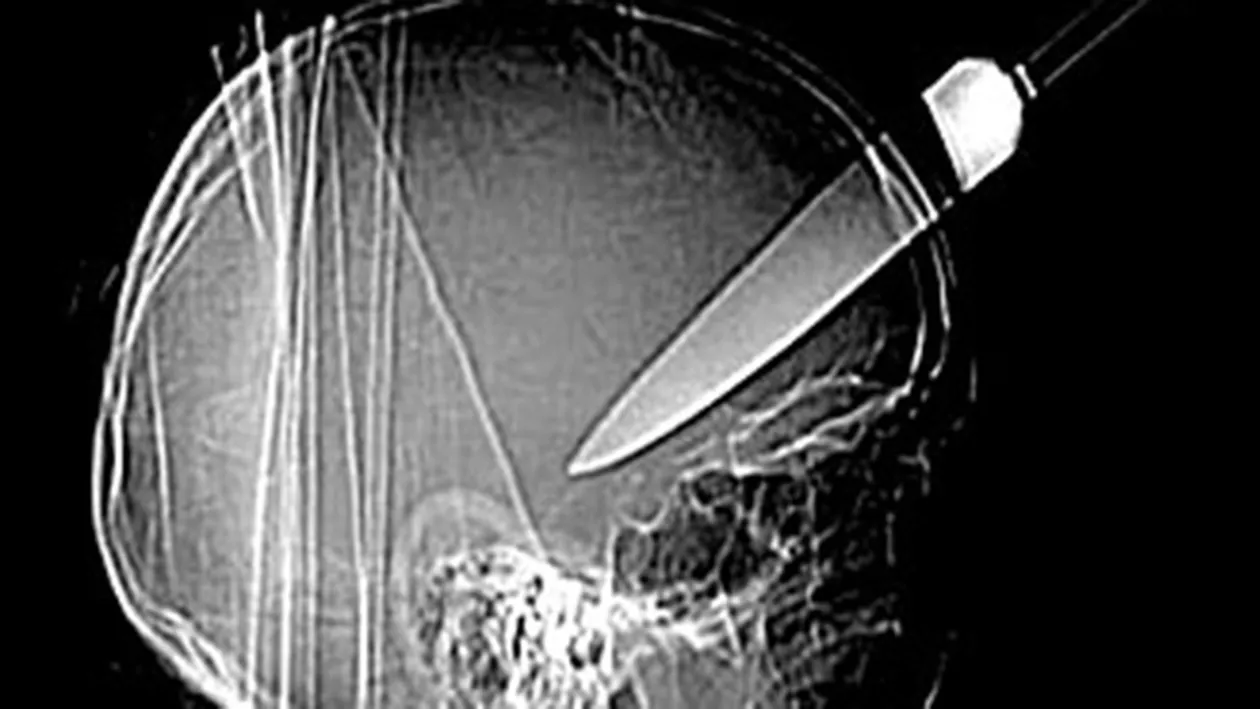

Desi pare greu de crezut, bărbatul a trăit cu un cutit in cap timp de 10 ani. Medicii i-au făcut o radiografie, iar rezultatele i-a lăsat de-a dreptul fără cuvinte. Lama cutitului avea o lungime de 10 centimentri, iar omul nu si-a dat nicio secundă seama că ar putea avea asa ceva in cap.

In cele din urmă, el si-a amintit că, in urmă cu 10 ani cand era taximetrist, a fost victima unui jaf. Bărbatul a fost bătut crunt, iar a doua zi a simtit o durere in locul in care a fost infipt cutitul, dar nu s-a dus la medic.

Totusi, omul a avut noroc, deoarece lama era foarte aproape de o artera care transporta sangele pe creier.